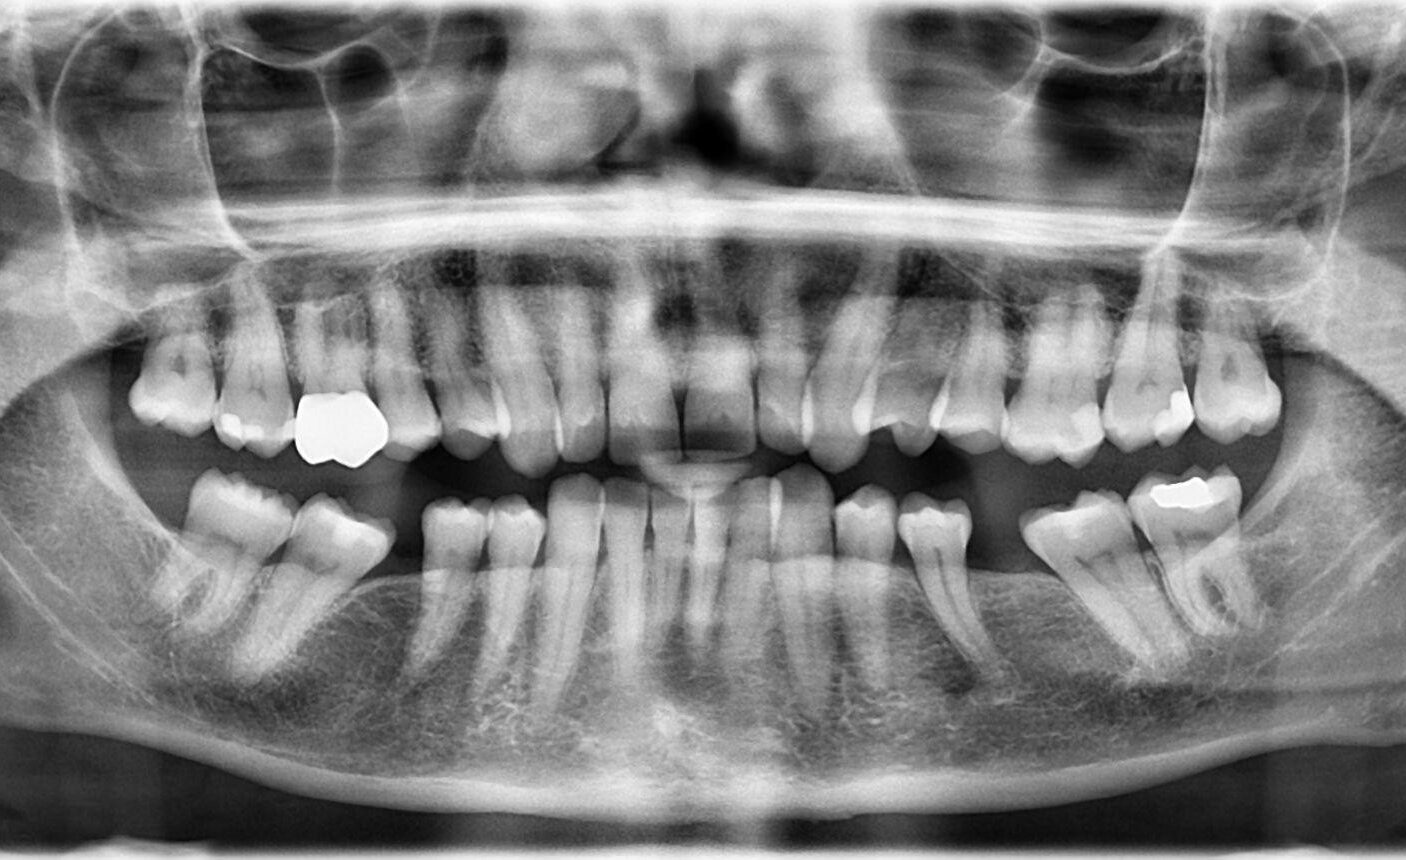

4. What option can be selected for upper jaw of this panoramic X ray?

5. What option cannot be selected for lower jaw of this panoramic X ray?